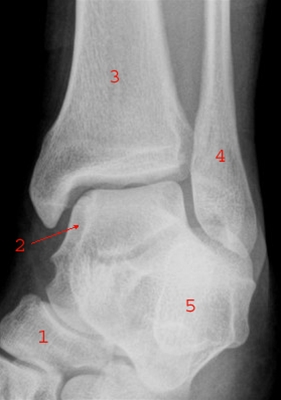

Ankel, skrå røntgenoptagelse

1. Os naviculare (bådbenet)

2. Talus (rullebenet eller springbenet)

3. Tibia (skinnebenet)

4. Fibula (lægbenet)

5. Calcaneus (hælbenet)